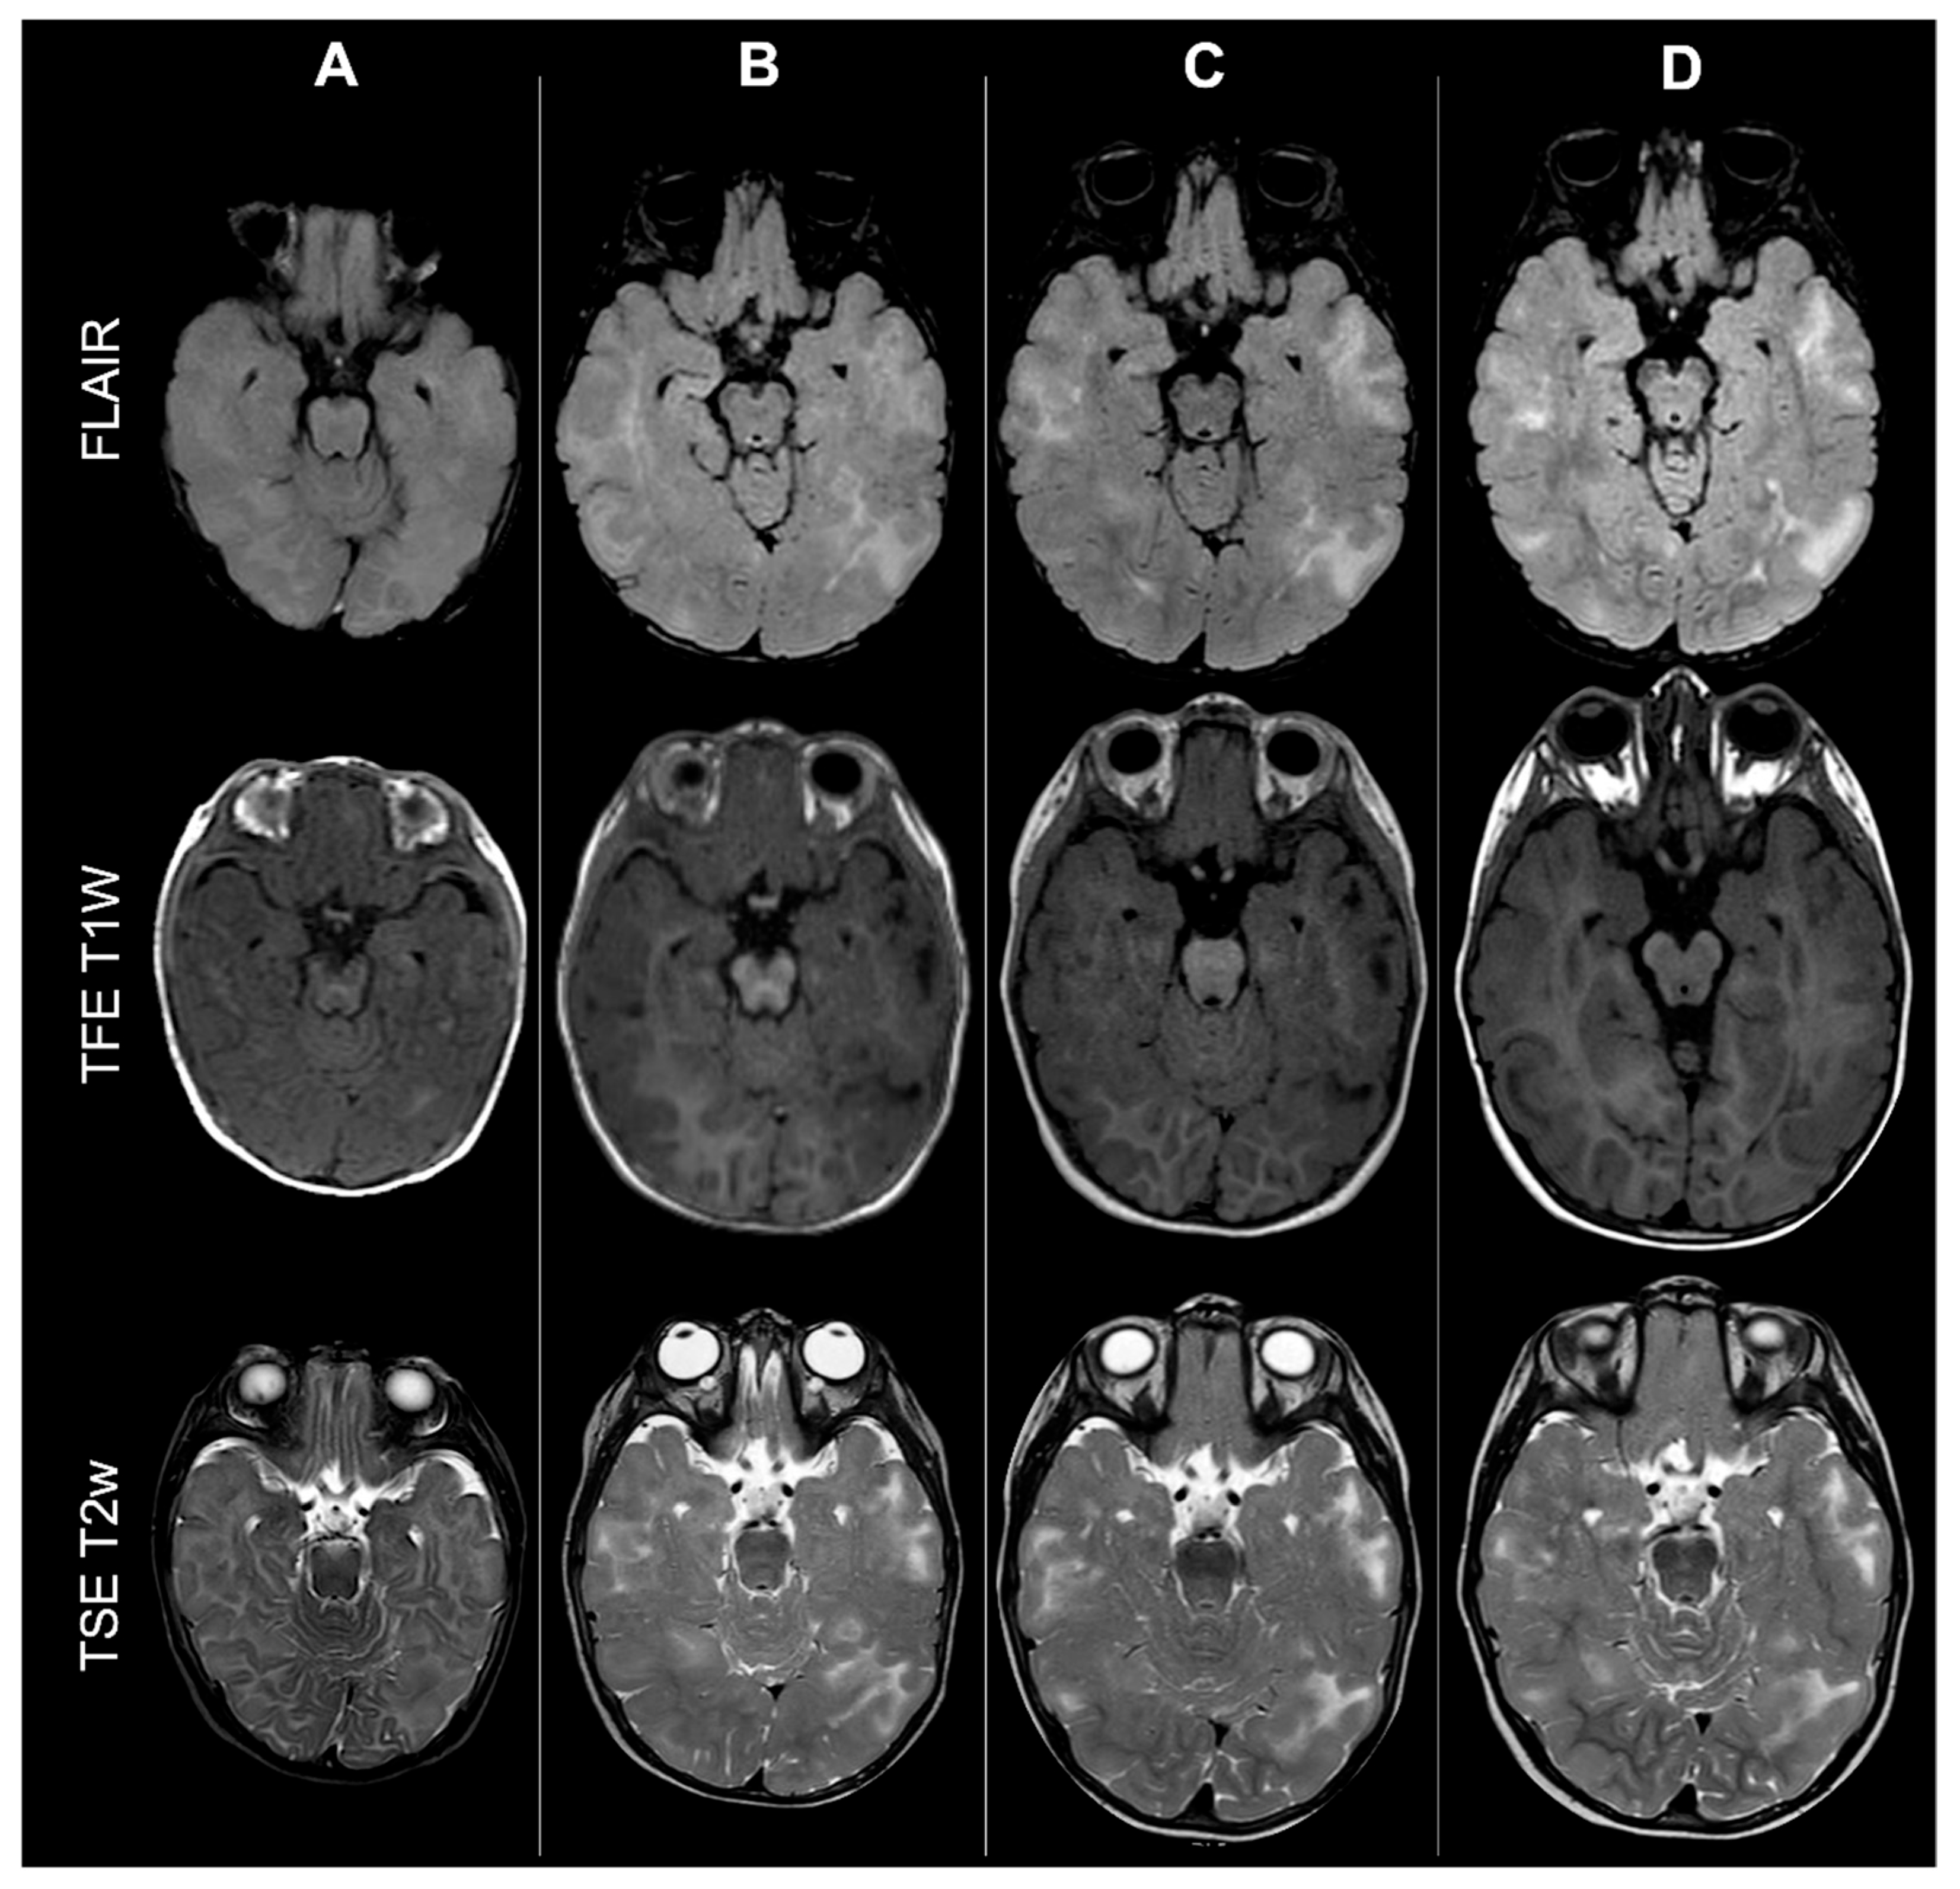

Given the potential role of brain maturation in influencing CT detection and classification, patients were subsequently stratified into two age-defined subgroups according to myelination status (<2 years vs. ≥2 years at baseline). An example of the effect of incomplete myelination on cerebral CTs count based on MRI scan is shown in Figure 5.

Figure 5.

Effect of myelination on cerebral cortical tubers’ count: MRI scans from the same male TSC2 patient acquired at four different timepoints (respectively: 6 months old—column A; 18 months old—column B; 36 months old—column C; 4 years old—column D, showing how incomplete myelination in early infancy may impact tubers detection by reducing contrast with surrounding brain tissue.